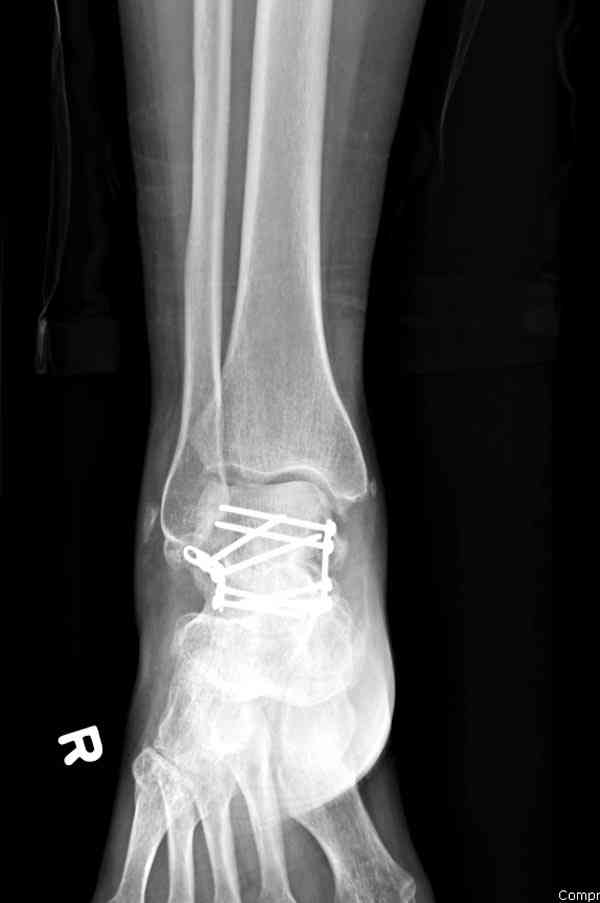

Случай с множественным оскольчатым переломом тарана оперированный из двойного доступа.

Через 8 мес.: